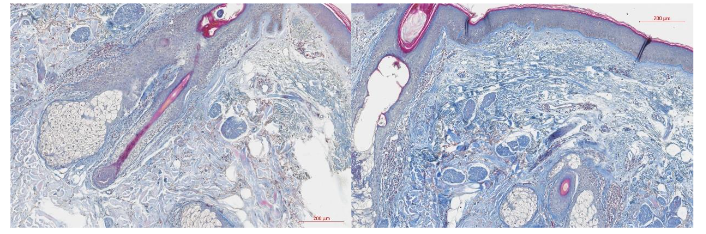

The average area occupied by collagen in the ROI was 192850.2 µm² at baseline. At a 3-month follow-up visit, the average collagen area had significantly increased to 269083.8 µm² (p-value = 0.0045). Compared to the baseline, the average collagen density was increased by 39.53% at a 3-month follow-up. The observed changes in the examined histology slices are visualized in Figure 1.

The average elastin-occupied area at baseline was 111063.8 µm² in the ROI. At the 3-month follow-up visit, the average elastin amount increased to 255492.5 µm² (p-value = 0.0009). Compared to baseline, the average elastin density was increased by 130.04% at 3-month follow-up. The observed changes in the examined histology slices are visualized in Figure 2.

The average area occupied by HA at baseline was 310354.8 µm² in the ROI. At a 3-month follow-up visit, the average HA-occupied area significantly increased by 230.02% to 1024219 µm² (p-value = 0.0017) in the ROI. The observed changes in the examined histology slices are visualized in Figure 3.